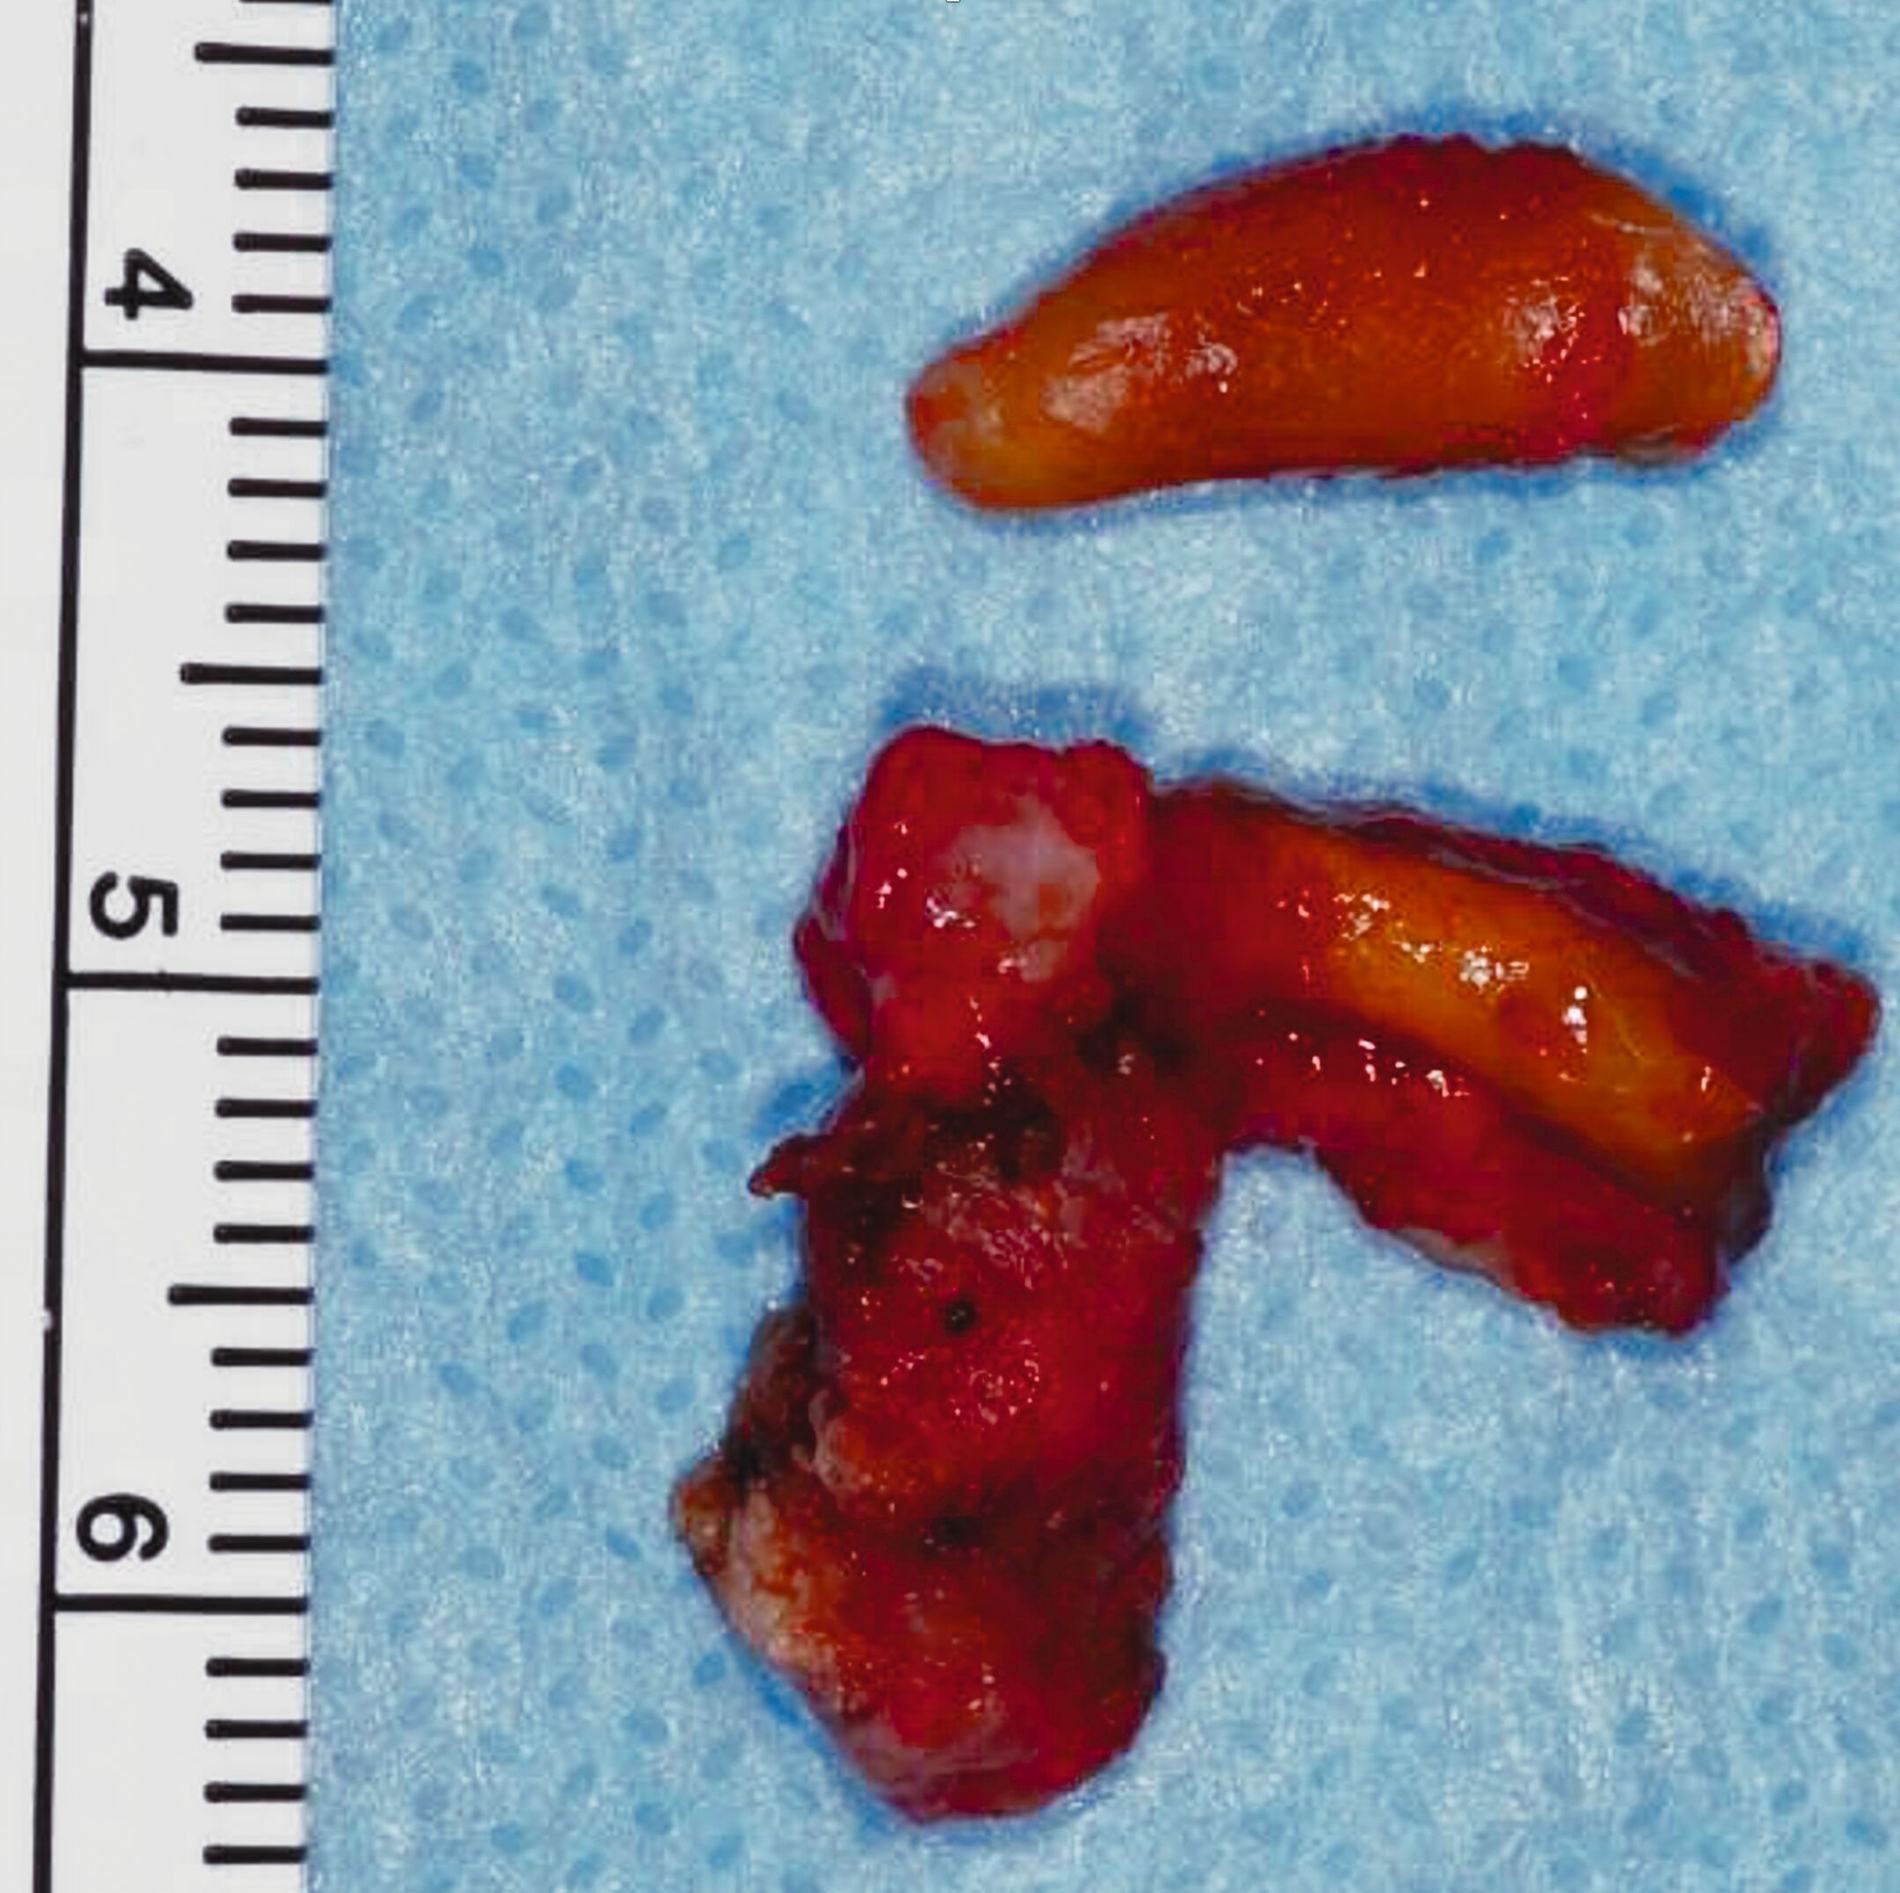

Nach der Planung des Eingriffs wurde der Patient in Intubationsnarkose operiert. Unter vorsichtiger Präparation und Darstellung des Alveolarknochens in Regio 37 ließ sich der bereits sonografisch beschriebene Fistelgang darstellen (Abbildung 5). Anschließend wurde Zahn 37 extrahiert und der entstandene Fistelgang chirurgisch revidiert (Abbildung 6). Die histopathologische Aufbereitung ergab dicht lymphoplasmazellulär infiltriertes Bindegewebe mit zystischer Aufweitung und einer epithelialen Auskleidung. Nach Abschluss der Wundheilung zeigte sich ein zufriedenstellendes kosmetisches Ergebnis ohne Anzeichen eines Rezidivs. Die Wurzelfüllung an Zahn 36 wurde in der Folge revidiert und in der Kontrollaufnahme nach einem Jahr waren keine Auffälligkeiten mehr zu erkennen.